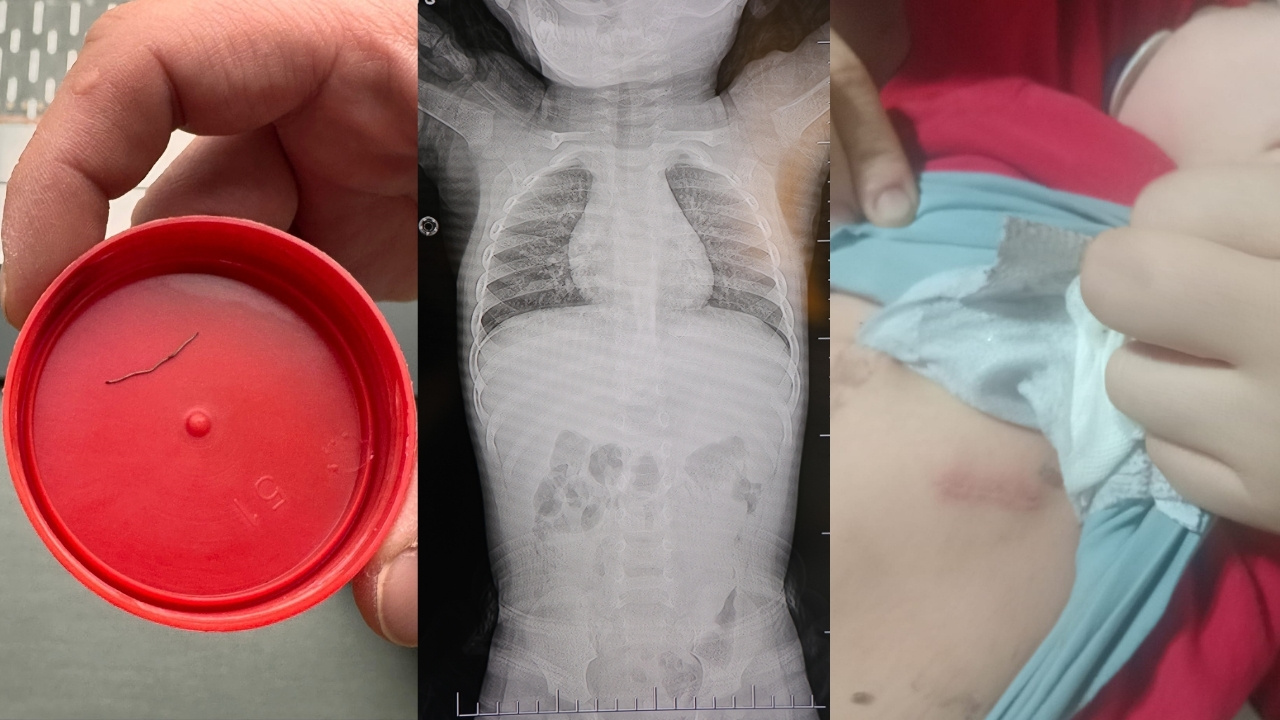

Kahramanmaraş’ta bir yaşındaki bebeğin belinden akciğer zarına doğru ilerlediği belirlenen 2 santimetrelik zımba teli ameliyatla çıkarıldı. Aile, bebeklerinin doğumundan bu yana süren ağlama ve huzursuzluk şikâyetlerinin nedeninin aylar sonra ortaya çıktığını belirterek olayın araştırılmasını istedi. Dulkadiroğlu ilçesinde yaşayan Orhan ve Hatice Nur Poyraz çifti, çocuklarının doğum sonrası kuvöz sürecinin ardından eve geldikten sonra sürekli ağladığını, ancak yapılan ilk kontrollerde sorunun tespit edilemediğini ifade etti. Aile, ihmali olanların ortaya çıkarılması için suç duyurusunda bulundu.

Baba Orhan Poyraz, defalarca hastaneye başvurduklarını, çeşitli ilaçlar verildiğini ancak şikâyetlerin devam ettiğini söyledi. Zamanla bebeğin bel bölgesinde hassasiyet oluştuğunu belirten Poyraz, bir acil servis başvurusunda doktorun yabancı cisim şüphesi üzerine tetkik istediğini aktardı. Çekilen görüntülemelerde “L” şeklinde bir zımba telinin varlığının tespit edildiğini ifade etti.

Üç gün sonra bebeğin bayılması üzerine özel bir hastaneye başvurduklarını anlatan Poyraz, burada yapılan değerlendirmede yabancı cismin akciğer zarına doğru ilerlediğinin belirtildiğini ifade etti. Doktorların ameliyat kararı aldığını ve operasyonla zımba telinin çıkarıldığını kaydetti. Poyraz, “Filmlere baktılar, ‘L şeklinde zımba teli var, alınması lazım’ dediler” ifadelerini kullandı.